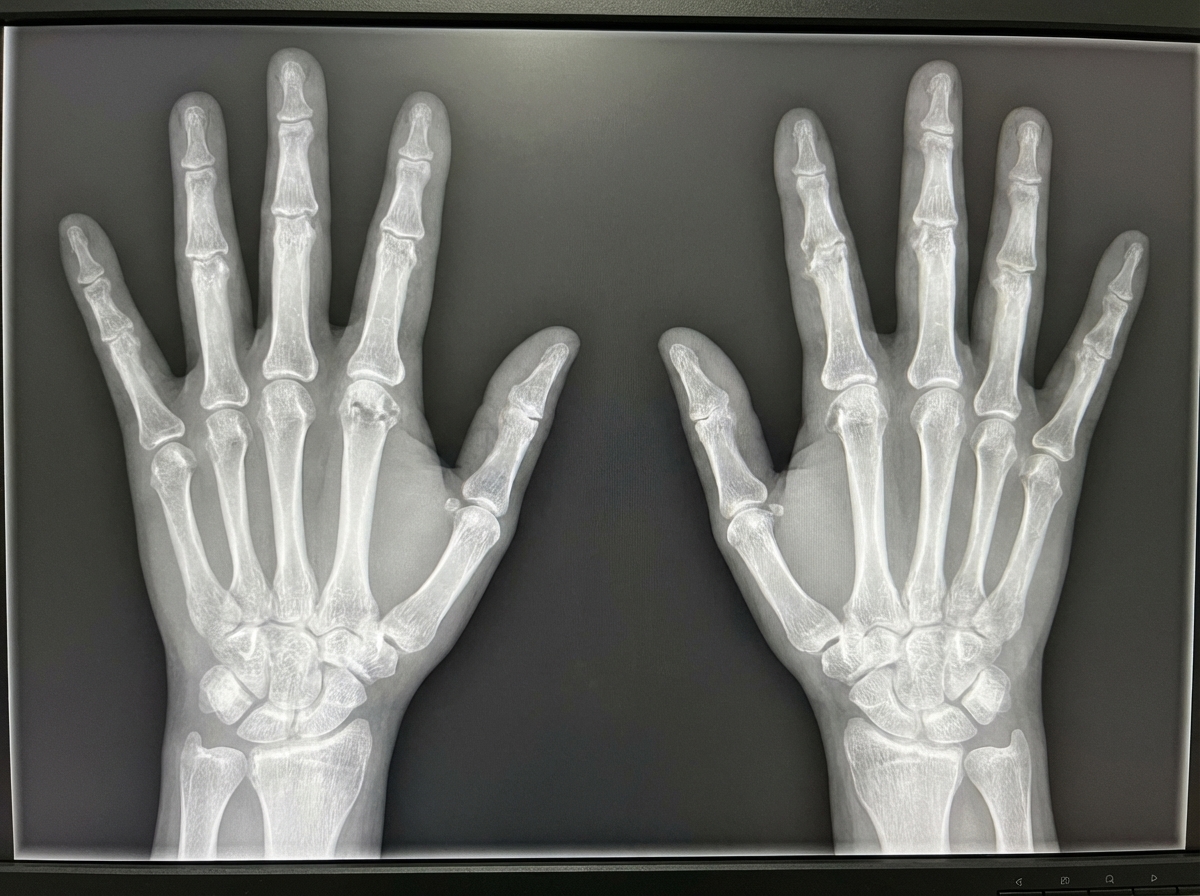

A patient suffering from morning stiffness lasting more than 1 hour presents with the following abnormality in the X-ray. What is the most possible diagnosis?

Explanation: ***Rheumatoid arthritis*** - **Morning stiffness lasting more than 1 hour** is a hallmark feature of RA, indicating significant **inflammatory synovitis**. - Classic X-ray findings include **periarticular osteoporosis**, **symmetric joint space narrowing**, and **marginal erosions** at **MCP/PIP joints**. *Psoriatic arthritis* - Typically presents with **asymmetric joint involvement** and characteristic **pencil-in-cup deformity** on X-ray. - Associated with **psoriatic skin lesions** and often affects **DIP joints**, unlike the pattern described. *Osteoarthritis* - Morning stiffness is typically **less than 30 minutes**, indicating mechanical rather than inflammatory pathology. - X-ray shows **osteophytes**, **joint space narrowing**, and commonly affects **DIP joints** with **Heberden's nodes**. *Relapsing polychondritis* - Primarily affects **cartilaginous structures** like ears, nose, and larynx rather than synovial joints. - Does not typically cause the **joint erosions** and **symmetric arthropathy** seen in inflammatory arthritis.